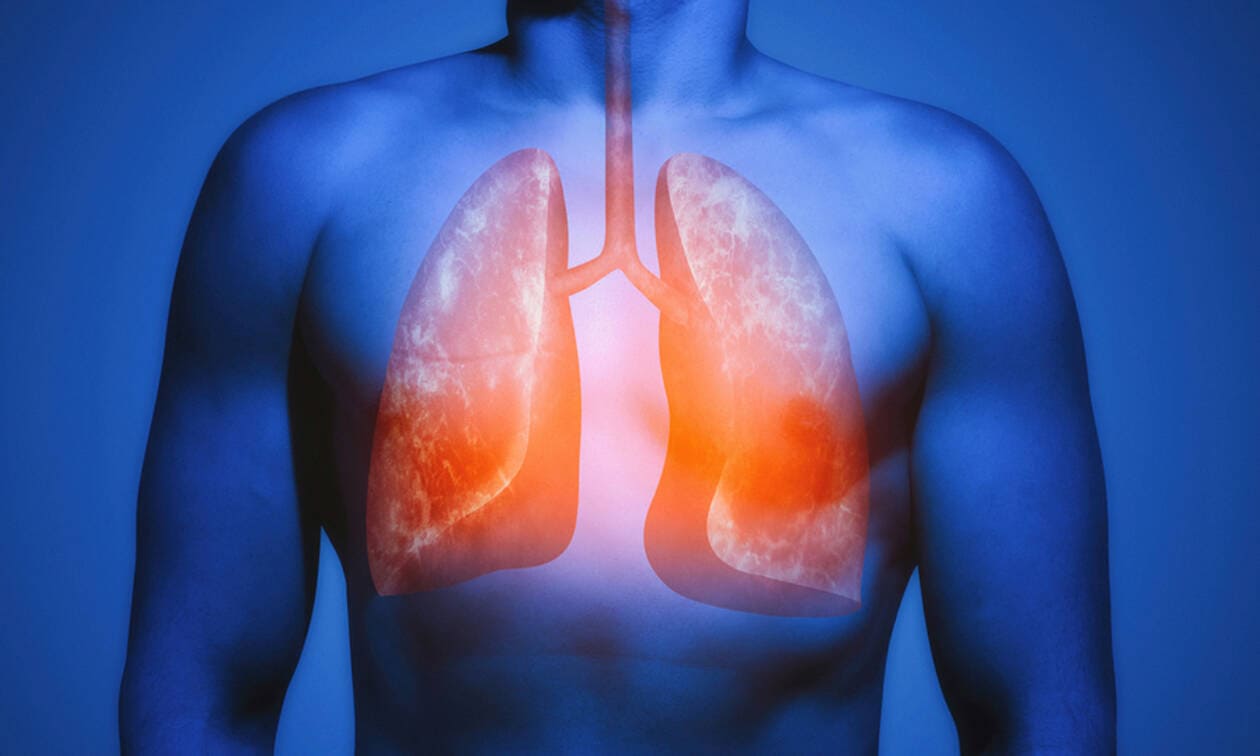

Μια νέα μελέτη, διαπίστωσε πως η κατανάλωση ψαριών ή συμπληρωμάτων ωμέγα-3 λιπαρών οξέων, ωφελούν την υγεία των πνευμόνων.

Προηγούμενες μελέτες έχουν δείξει ότι τα ωμέγα-3 λιπαρά οξέα μπορούν να βοηθήσουν στη διατήρηση της υγείας των πνευμόνων λόγω της αντιφλεγμονώδους δράσης τους.

Η μελέτη διαπίστωσε ότι τα υψηλότερα επίπεδα ωμέγα-3 λιπαρών οξέων στο αίμα συσχετίστηκαν με μειωμένο ρυθμό πτώσης της λειτουργίας των πνευμόνων.

Η έρευνα διαπίστωσε ότι τα υψηλότερα επίπεδα ωμέγα-3 λιπαρών οξέων, συμπεριλαμβανομένου του DHA, συσχετίστηκαν με καλύτερη λειτουργία των πνευμόνων.